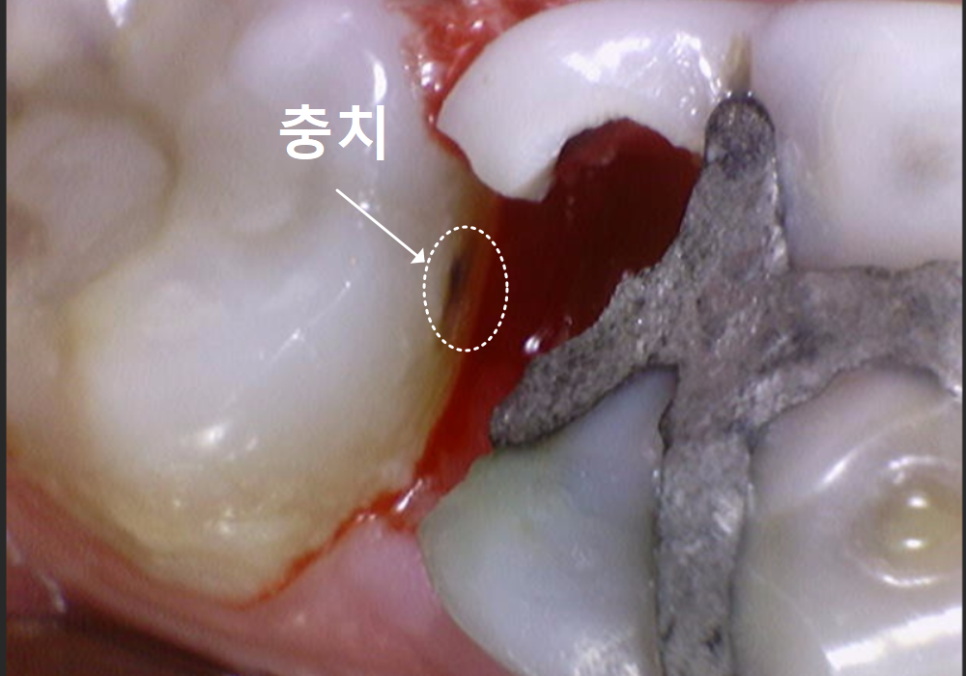

얼마 전 오른쪽 아래 어금니 통증으로

내원하신 환자분이 계셨어요.

입안을 자세히 살펴보니,

어금니(#46)의 윗면이 깨져,

그 틈으로 음식물이 꽉 끼어 있었어요.

음식물에 눌려있던 잇몸은 빨갛게 부어올라

살짝만 건드려도 피가 날 정도였어요.